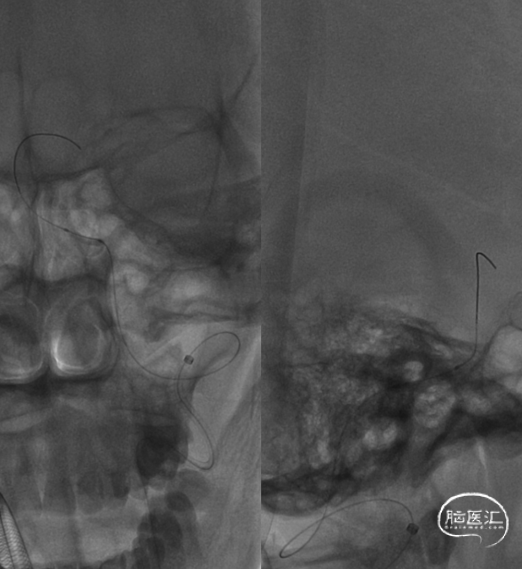

球囊到位。

球囊扩张。

球囊扩张后狭窄有所改善。

支架顺利到达病变位置到位。

充盈球囊,释放支架。

支架释放后。